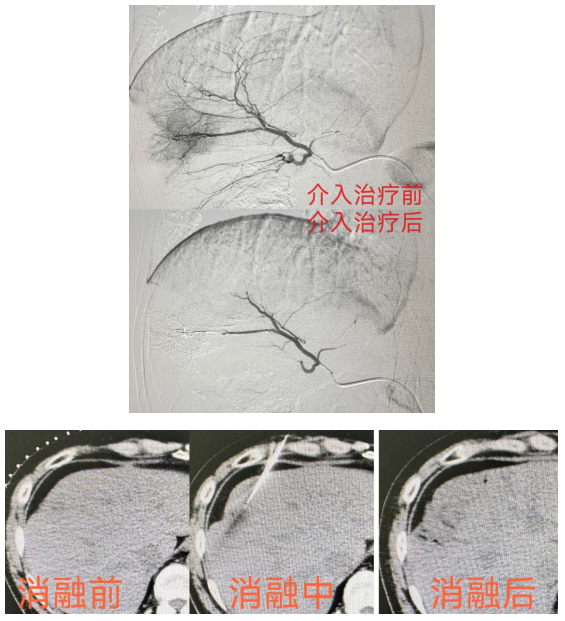

与此同时,肿瘤外二科团队针对朱先生的病情进行了MDT多学科会诊,先后给予其化疗联合靶向治疗、肝转移灶射频消融术和肝动脉灌注化疗栓塞术。治疗过程中,朱先生积极配合,通过多周期的治疗及肿瘤外二科医护人员的精心护理,朱先生与肿瘤的抗争获得了阶段性的胜利。

肝动脉灌注化疗栓塞术-TACE治疗是经皮穿刺动脉血管,用导管选择肝肿瘤靶血管后,经导管灌注化疗药,再用栓塞物质阻断肝肿瘤血供的治疗方法,是一种把肿瘤细胞“饿死”的介入治疗技术。

什么是肿瘤射频消融?

射频消融术(RFA)是一种通过热效应使肿瘤细胞死亡的肿瘤微创治疗技术,是在超声或CT 等影像设备引导下,将射频针准确插入肿瘤组织,通过射频电流激发组织内的离子产生高频振荡、相互摩擦产热,从而使肿瘤组织凝固性坏死,达到治疗肿瘤的目的。肿瘤射频消融治疗具有创伤小、安全性高、治疗费用低、可反复多次治疗、术后生活质量高等优点。